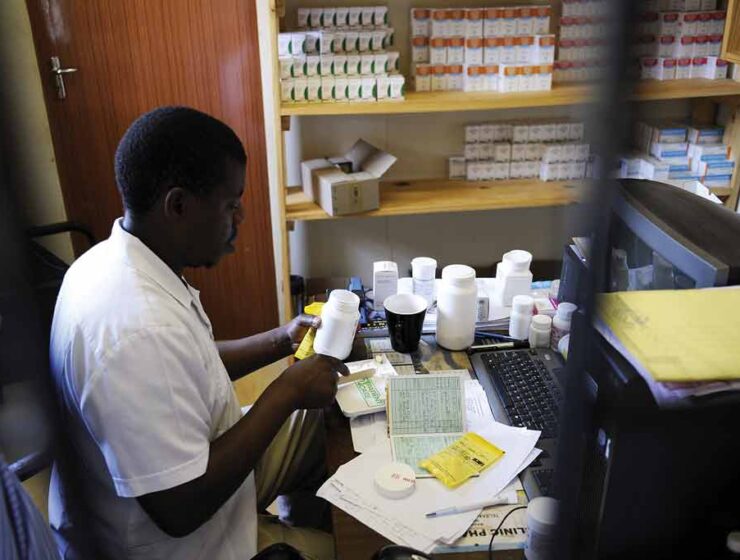

A healthcare system on ICU Shortage of resources, medication and manpower still a challenge P15…

• “Most clinics not providing ART and other contraception methods” • Ministry of Health failing…